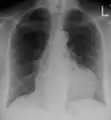

A pericardial effusion as seen on CXR in someone with pericarditis

The diagnosis of tamponade can be confirmed with trans-thoracic echocardiography (TTE), which should show a large pericardial effusion and diastolic collapse of the right ventricle and right atrium. Chest X-ray usually shows an enlarged cardiac silhouette ("water bottle" appearance) and clear lungs. Pulmonary congestion is typically not seen because equalization of diastolic pressures constrains the pulmonary capillary wedge pressure to the intra-pericardial pressure (and all other diastolic pressures).